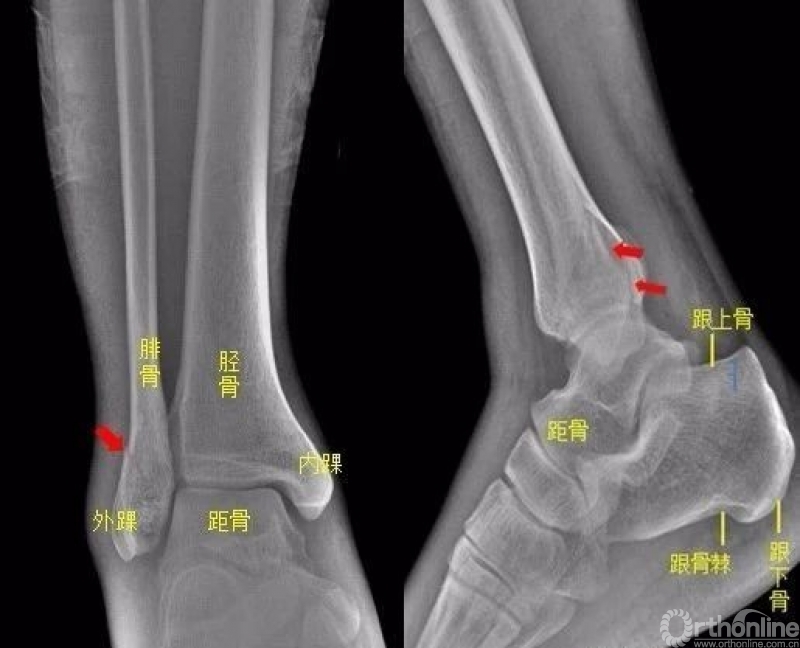

踝关节

右侧外踝骨皮质连续中断,可见透亮骨折线影,可见软组织稍肿胀影。右踝关节骨折

Warmreminder: 踝关节扭伤,许多大夫只做踝关节正侧位。有时踝关节正侧位不能看出有明显异常,而有局部软组织肿胀,活动受限时,根据我的经验,踝关节扭伤有时只做正侧位是有局限性的;小妙招足正位也是必不可少的。

此患者就是踝关节扭伤,踝关节正侧位未见异常,加拍足正位时发现外踝骨折。

所示右侧腓骨远端见斜行骨折线,骨折端对位对线尚可。右腓骨远端骨折。